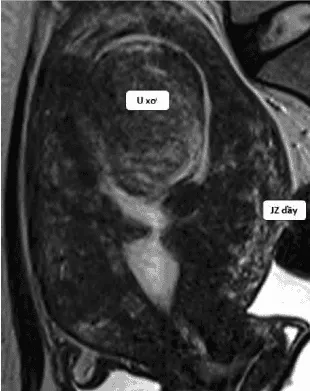

Tổn thương có thể khu trú tạo giả u xơ, hoặc kết hợp với u xơ thật, khó phân biệt.

Hình ảnh “Kết hợp adenomyosis và u xơ tử cung”.

MRI: Phân biệt adenomyosis vs u xơ, đánh giá lạc nội mạc sâu.